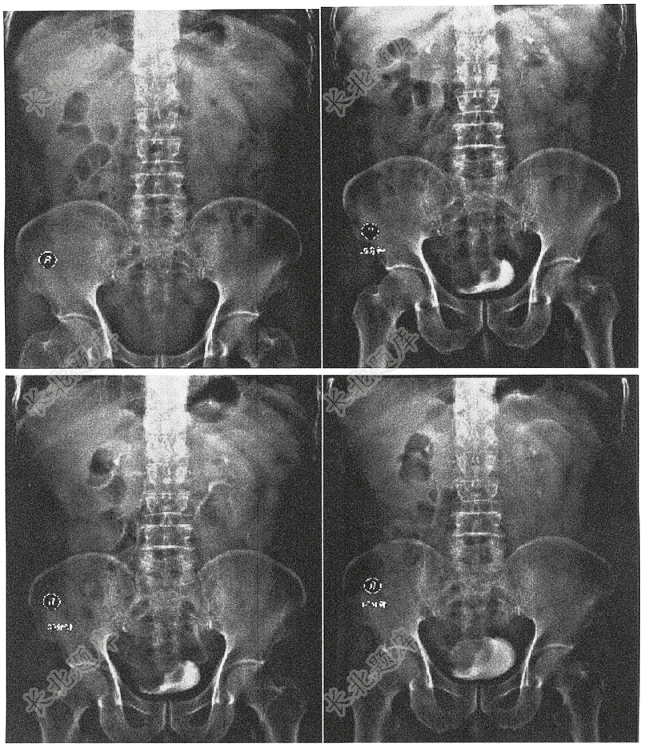

- 简答题患者男,75岁,反复排全程无痛性肉眼血尿4月余,

- 女,56岁。主诉:双侧腰痛1年,肉眼血尿